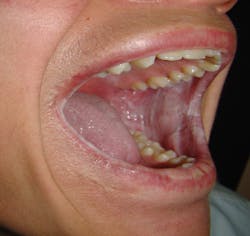

Clinical appearance: The patient will exhibit heavy white plaques mainly on the buccal and labial mucosa that are asymptomatic. The white plaques may also appear on the floor of the mouth, tongue, and alveolar mucosa with rare occurrence on the palate. Heavy, thickened tissue may compromise mastication. Less common areas such as nasal, esophageal, laryngeal, and anogenital mucosa may be affected.

White Sponge Nevus. Courtesy of Doron Aframian, DMD, PhD.

Images courtesy of Murat Songu, MD, department of otorhinolaryngology, Dr. Behcet Uz Children's Hospital in Izmir, Turkey.